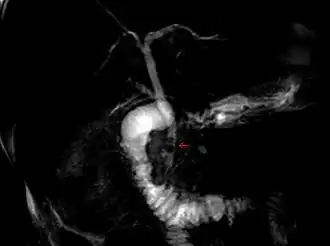

Coledocolitiasis

Cálculos impactados en el conducto biliar común (flecha roja). | ||

La coledocolitiasis es la presencia de cálculos en la vía biliar principal. Los cálculos así impactados pueden ser pequeños o de gran tamaño, únicos o múltiples y tienden a aparecer en un 6-12% de los pacientes con colelitiasis.[1]